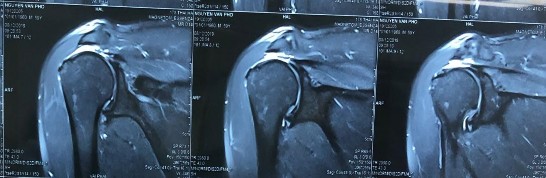

Bệnh nhânn nam 62 tuổi, tiền sử khoẻ mạnh. Bệnh nhân bị chấn thương vai phải sau đập mạnh cầu lông cách nhập viện 06 tháng, sau thấy đau nhiều vai, hạn chế vận động. Do là bác sĩ chuyên về nội xương khớp lên bệnh nhân tự điều trị uống thuốc và tiêm khớp tuy nhiên không thấy tiến triển. Bệnh nhân đến khám và nhập viện ngày 24/02/2020. Khám thấy đau âm ỉ vùng vai, vai hạn chế giạng và đưa trước khoảng 70 độ, hạn chế xoay trong và hạn chế xoay ngoài. Khám các test phát hiện chèn ép khoang dưới MCV và tổn thương gânn chóp xoay thấy: Neer test (+); Speed test (-); Jobe test (+); Patte test (+); Drop arm test (-); Bear Hug test (-), trên phim MRI chụp trước mổ có hình ảnh rách rất rộng và co rút gân chóp xoay đỉnh ổ chảo. Bệnh nhân được tiến hành phẫu thuật khâu gân chóp xoay ngày 25/02/2020. BN sau mổ được mặc áo vai trong 06 tuần, tập phục hồi chức năng. Đánh giá điểm ASES trước mổ và sau mổ là 30 và 96,67 điểm UCLA sau mổ là 33, bệnh nhân rất hài lòng và cảm thấy tốt hơn so với lúc chưa mổ.

Hình phụ lục 2A: Phim CHT bệnh nhân trước mổ cho thấy rách lớn và co rút gân trên và dưới gai trên phim cắt mặt phẳng trán.

(Nguồn: BN nghiên cứu)